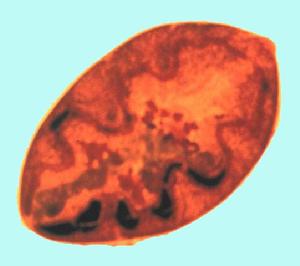

華支睪吸蟲病成蟲蠕動緩慢,大多吸附於膽管內壁黏膜。其蟲卵是人體寄生蟲卵中最小的一種,約為(27.3~35.1)μm×(11.7~19.55)μm,呈橢圓形,略似電燈泡狀,殼厚,呈棕黃色,一端有陷入於卵殼中的小蓋,在連線處卵殼增厚,卵內含一個毛蚴。成蟲寄生於宿主的肝內中、小膽管內,有時移居較大膽管或膽總管,大都是吸附於膽管內壁的黏膜,以組織液和黏液中的葡萄糖或蛋白質為營養,營有性生殖。